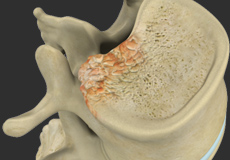

Vertebral Compression Fractures

Back pain is an indication of stress fractures known as vertebral compression fractures. Vertebral compression fractures occur when the normal vertebral body of the spine is squeezed or compressed. The bone collapses when too much pressure is placed on the vertebrae, resulting in pain, limited mobility, loss of height and spinal deformity.

Spinal Fractures

Vertebral compression fractures occur when the normal vertebral body of the spine is squeezed or compressed. The bone collapses when too much pressure is placed on the vertebrae, resulting in pain, limited mobility, loss of height, and spinal deformities.

Osteoporosis of the Spine

Osteoporosis is a bone disease characterized by a decrease in bone mass and density resulting in brittle, fragile bones that are more susceptible to fractures. The condition most commonly affects elderly women. Osteoporosis-related fractures are more common at the vertebral bodies of the spine.